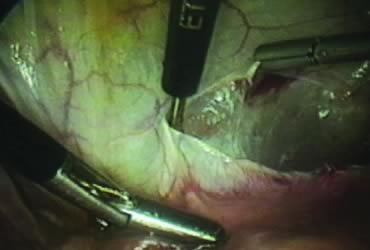

Isolation of the Adnexa

A window is created in an areolar avascular area of the broad ligament with gentle blunt dissection. The adnexal structures above the window are coagulated (or sutured) and cut, isolating the adnexa and detaching it from the uterus (Fig. 6). The procedure is repeated in the contralateral side.

Fig. 6. Creation of a window in the broad ligament.